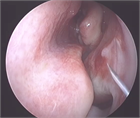

1. 鼻中隔彎曲症とは、鼻腔を左右に分ける鼻中隔が彎曲することによって鼻閉などの鼻症状を引き起こす疾患である。

1. 成長に伴い彎曲が生じたものと、外傷に伴い彎曲が生じたものに大別され、症状としては鼻閉が高頻度に認められ、鼻閉に伴う嗅覚障害や鼻出血を認めることもある。鼻中隔彎曲に伴い外鼻が変形し斜鼻などの美容的問題を訴える患者も認める。